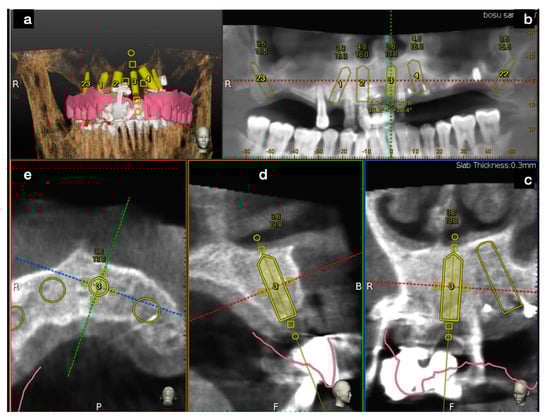

3.1. SCAI Approach Clinical Case